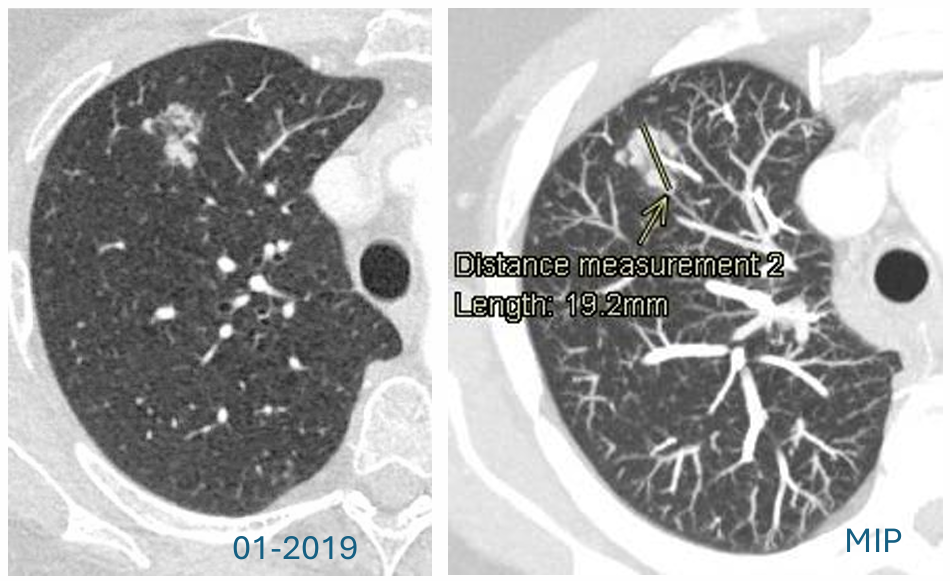

长期随访:病情逆转

2020年10月,CT随访:距离上次“缩小”的CT检查11个月后,复查CT显示,病灶出现戏剧性的逆转。影像表现:原先缩小的亚实性结节出现显著增大。关键变化:其内部的实性成分在11个月内,从3mm快速增长至11mm。这种实性成分的明确增长是恶性肿瘤的明确信号,至此已基本排除良性炎性病变的可能性。

bf6598b6-23e8-4f8e-80a6-ad367a4363ef.png

治疗与转归

确诊后,患者接受VATS进行肺叶切除术,术后病理显示,pT1cN0M0(分期表明为早期、无淋巴结转移、胸膜侵犯阴性、切缘阴性的完全切除)。截至2021年12月(术后1年余),CT复查未见肿瘤复发或继发性肿瘤。

25231391-65ed-4308-a9fa-da0809f88618.png